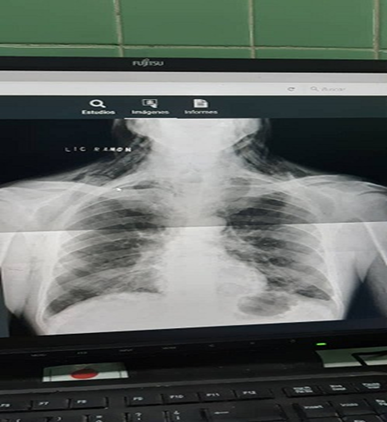

En el Cuerpo de Guardia se le realizó radiografía de tórax, en la que se observaron pequeñas opacidades bilaterales de aspecto inflamatorio. En el pulmón derecho, una de las imágenes mostraba tendencia nodular de aproximadamente 1 cm.

Índice cardiotorácico (ICT): normal.

Se realizó rayos X de tórax que informó presencia de enfisema celular subcutáneo e imagen sugerente de neumomediastino (Figura 3), por lo que se indicó estudio tomográfico de tórax que informó presencia de aire en todos los compartimientos del mediastino, enfisema subcutáneo en las paredes anterior, posterior y laterales del tórax. (Figura 4).